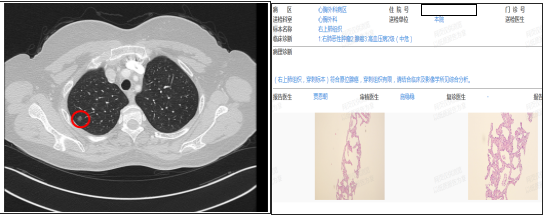

两年前,52 岁的彭女士(化名)在体检中发现右肺上叶存在 8mm 磨玻璃结节。在后续随访过程中,结节实性成分不断增多,经影像学检查提示存在早期肺癌可能性。出于对治疗效果的信任,彭女士慕名前往漯河市中心医院心胸外科就诊。马广耀团队接诊后,对其病情展开详细分析,综合评估结节的影像学表现及变化趋势,最终建议采取手术切除方案。考虑到彭女士较为年轻,对术后美观和恢复速度有着较高期待,手术团队经深入讨论,决定采用经乳房下皱襞微单孔胸腔镜肺病损切除术,为其定制微创与美观兼具的治疗方案。

手术当日,马广耀团队在彭女士乳房下皱襞处切开约 2.0cm 的弧形切口,以此为通道顺利完成右上肺病损切除与纵隔淋巴结采样术。术后,切口巧妙隐藏于乳房折皱处,从外观上几乎无法察觉,真正实现了手术切口 “隐形”。